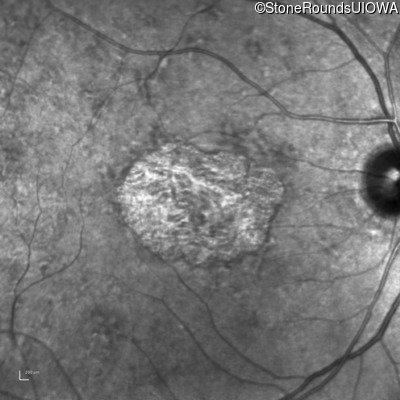

Pattern Dystrophy (IIC)

This 47 year man first experienced some decrease in his central vision about 10 years ago.

Diagnosis & molecular findings

Pattern Dystrophy PRPH2 Gly167Asp GGC>GAC   AD